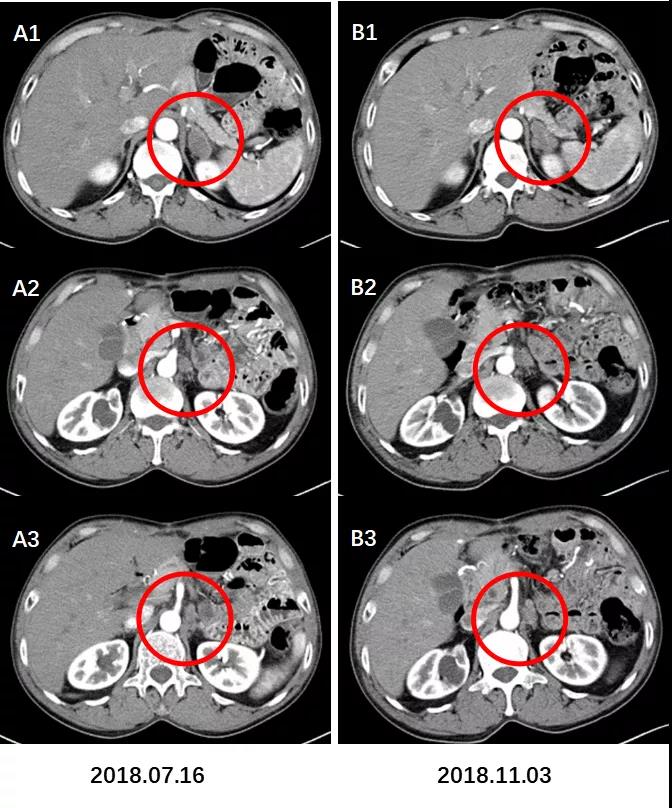

全腹部CT增强扫描(2018.11.03):前片所示肝内多发低密度灶未见明显显示。左侧肾上腺区及腹膜后多发肿大淋巴结,转移考虑,较前片增多增大。

图7. 肝脏转移灶基本消退。

A:术后CT增强(2018.07.16)示肝脏多发转移灶。B:术后CT增强(2018.11.03)示肝脏转移灶基本消退。

图8. 左肾上腺区,膈下及腹膜后淋巴结较前增大增多。

术后CT增强(2018.11.03)B1示左肾上腺区转移灶较前片(2018.07.16)。A1略增大;B2,B3示膈下及腹膜后淋巴结转移较A2,A3增大增多。

(3)疗效评价:PD。